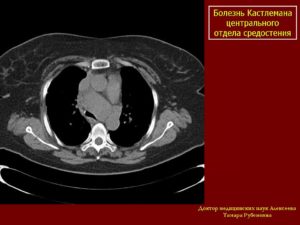

Кт и мрт диагностика болезни кастлемана

- Опухолевидные массы в средостении и/или прикорневой области.

Гиалиново-сосудистый тип:

- характерно выраженное гомогенное контрастное усиление пораженных лимфатических узлов (гомогенность нарушается при некрозе, фиброзе и дистрофии);

- может присутствовать питающий сосуд

- Изменения отмечаются преимущественно в среднем и заднем средостении и в прикорневой области (переднее средостение поражается редко)

- В 5—10% случаев выявляют очаги обызвествления.

Плазмоцитарный тип:

- Контрастное усиление выражено в значительно меньшей степени.

- помимо внутригрудных лимфатических узлов поражаются также лимфатические узлы брюшной полости и забрюшинного пространства, реже — шеи

Болезнь Кастлемана у женщины 30 лет.

На обзорной рентгенограмме грудной клетки видна опухоль с четко очерченными полициклическими контурами, локализующаяся в воротах правого легкого, которая не беспокоила больную и была выявлена случайно. Рентгенологически опухоль невозможно отличить от лимфомы и опухолей другой этиологии.

При гиалиново-сосудистом типе болезни Кастлемана выраженное контрастное усиление пораженных лимфатических узлов на КТ может помочь установлению типа лимфомы.